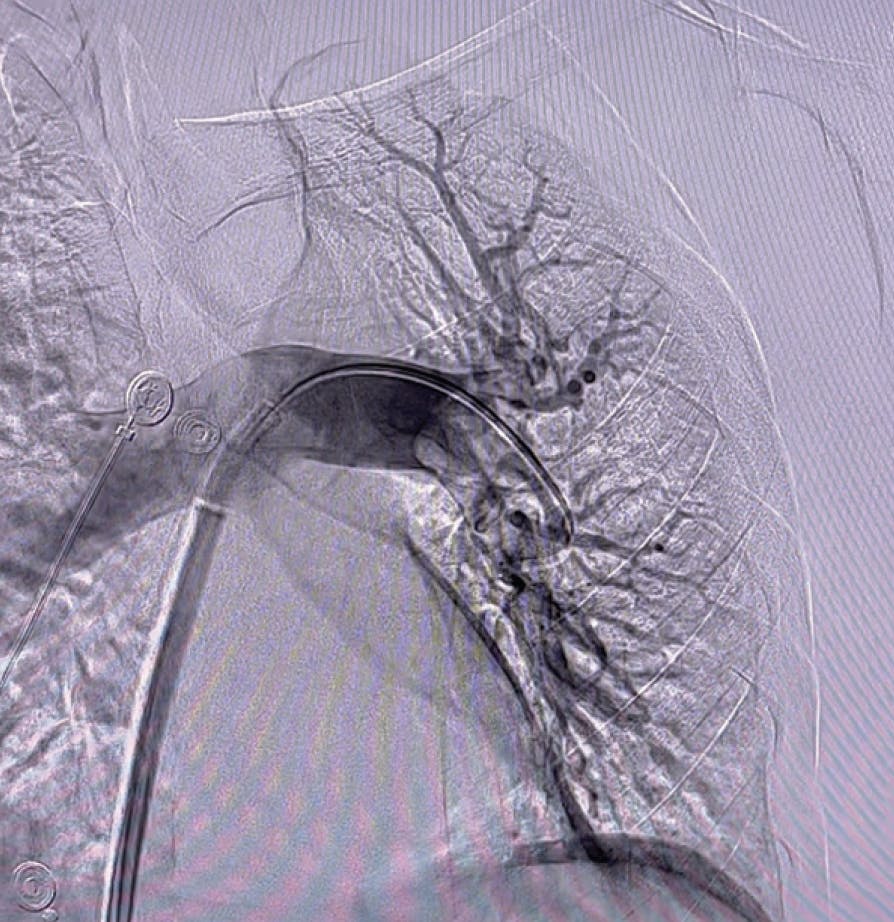

Figure 1. Right lobe initial angiogram.

Figure 2. Left lobe initial angiogram.

Figure 1. Right initial angiogram.

Figure 2. Left initial angiogram.